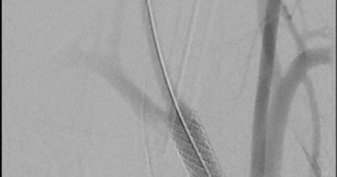

#aortaed. Early branches pose challenges for maintaining adequate endovascular seal. Here we demonstrate one technique for ensuring seal without having to embolize large branches by utilizing the BeBack catheter to perforate a VBX stent. **off label**

Sometimes you have to move a couple of branches out of the way… #aortaed @DrZeigler1 @MUSCVascular